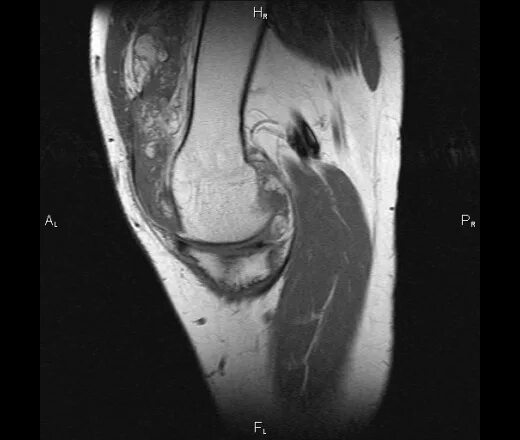

Пигментный виллонодулярный синовит